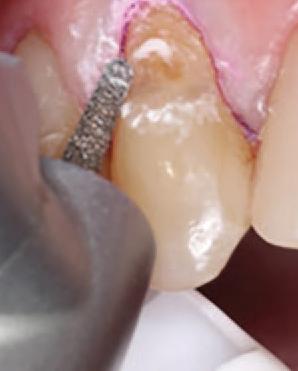

To improve isolation and soft tissue access, a retraction cord was placed before initiating the procedure (Fig. 2). The tooth was evaluated using a caries indicator dye (Kuraray Noritake Dental), helping to identify any remaining infected tissue beneath the dislodged composite (Fig. 3). Decay removal was completed with a diamond bur, and the enamel was bevelled using a starburst pattern to enhance aesthetic blending (Fig. 4). This preparation design was chosen for visual integration rather than bond strength enhancement.